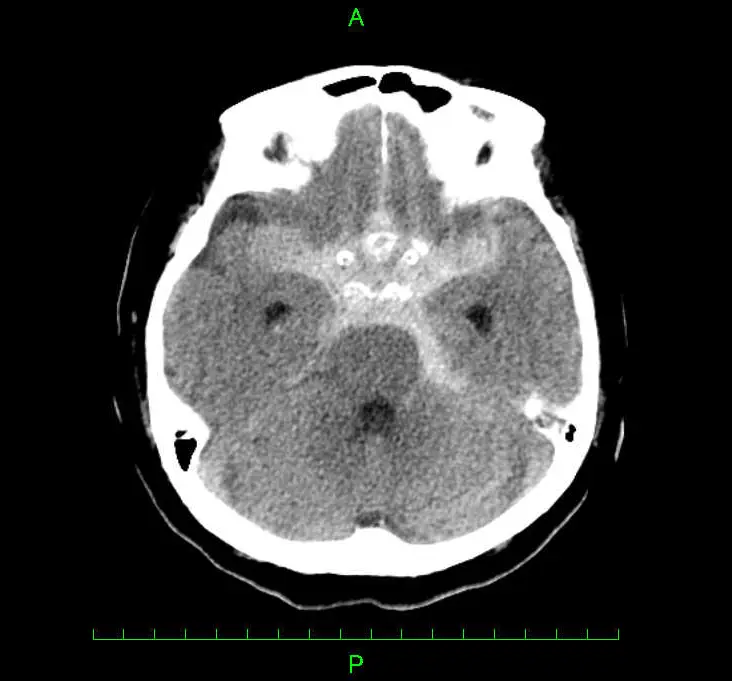

頭部CT検査を用います。CTでくも膜下出血と診断された場合は、原因の特定等を目的に造影検査やMRI検査などを行います。